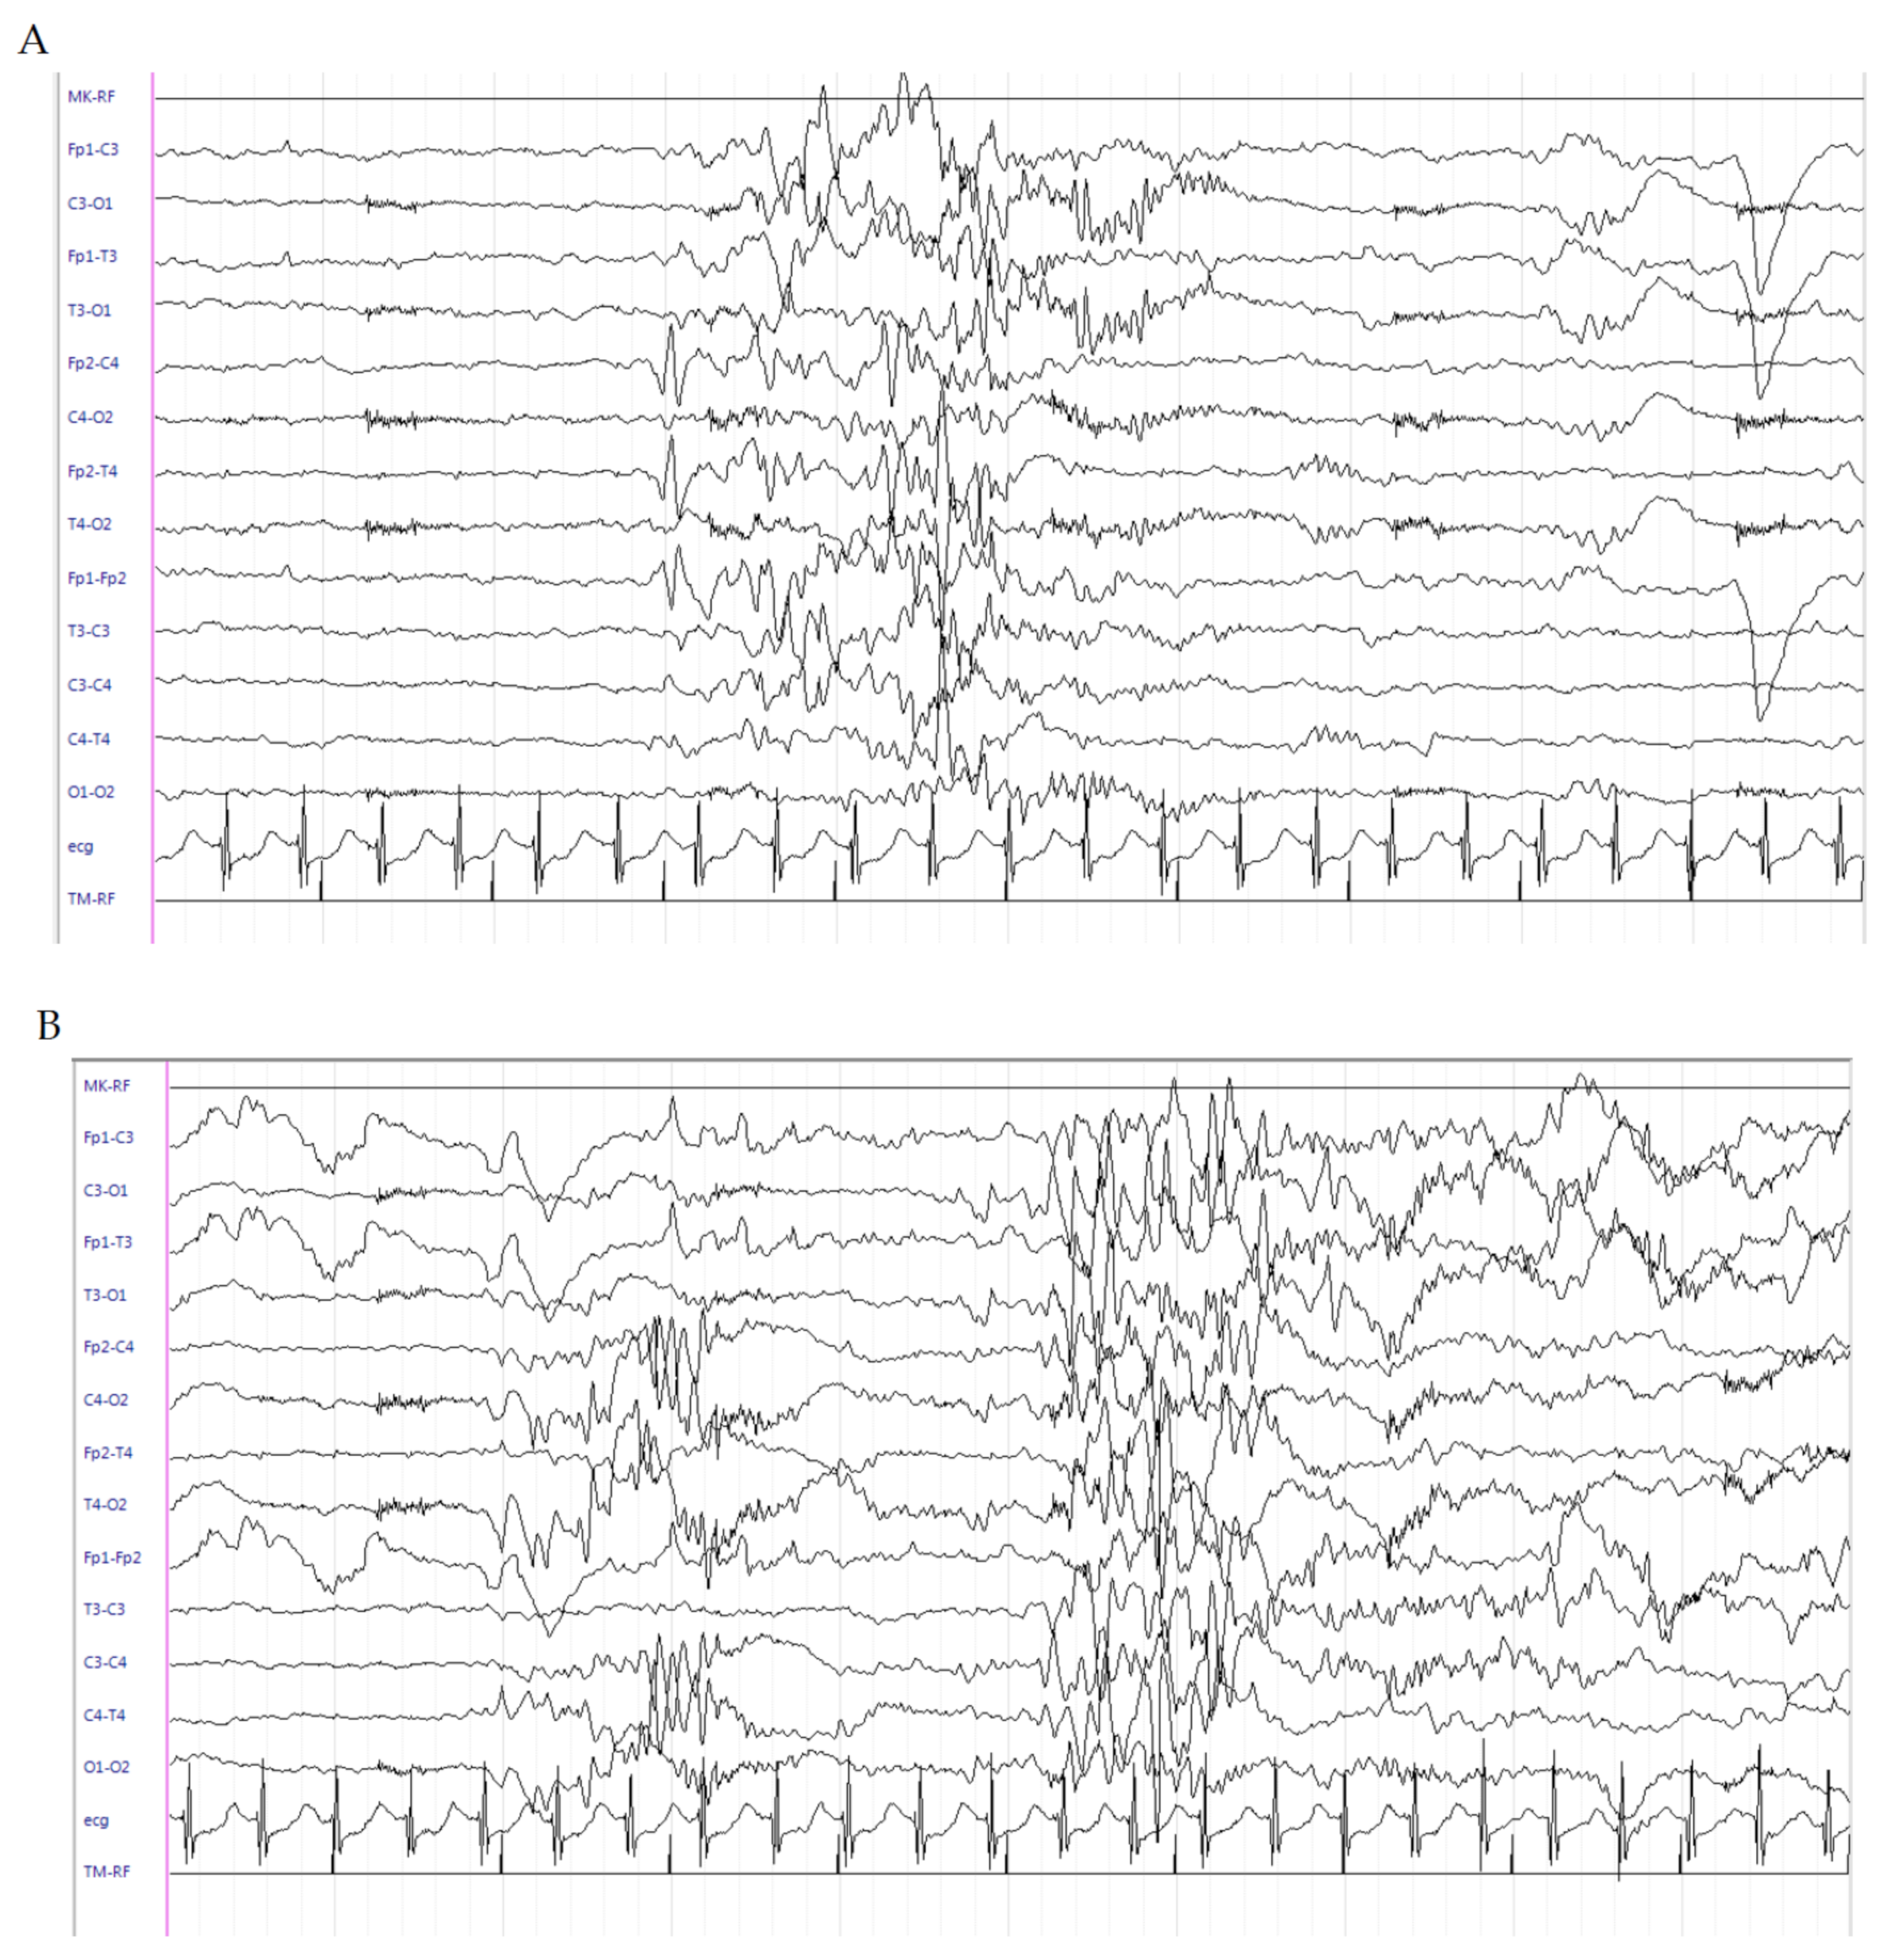

2.1. Patient 1

2.2. Patient 2

2.3. Patient 3